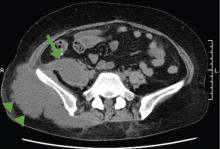

A cancer patient receiving corticosteroids for a brain metastasis developed emphysematous cystitis and psoas muscle abscess.

The patient was admitted to the hospital for percutaneous drainage, which produced 26 mL of pus on the first day and 320 mL on the next day; culture was positive for Escherichia coli. Urine culture was also positive for E coli; blood culture was not. We concluded that these results were secondary to pyelonephritis.

Inflammatory markers such as erythrocyte sedimentation rate and C-reactive protein may be elevated in all patients with iliopsoas abscess, so if those markers are not elevated, we may have to consider other conditions such as cancer.1 Computed tomography is nearly 100% sensitive for iliopsoas abscess and is the gold standard for diagnosis.3

The average size of the abscess is 6 cm. Percutaneous drainage is required if the mass is larger than 3.5 cm.1